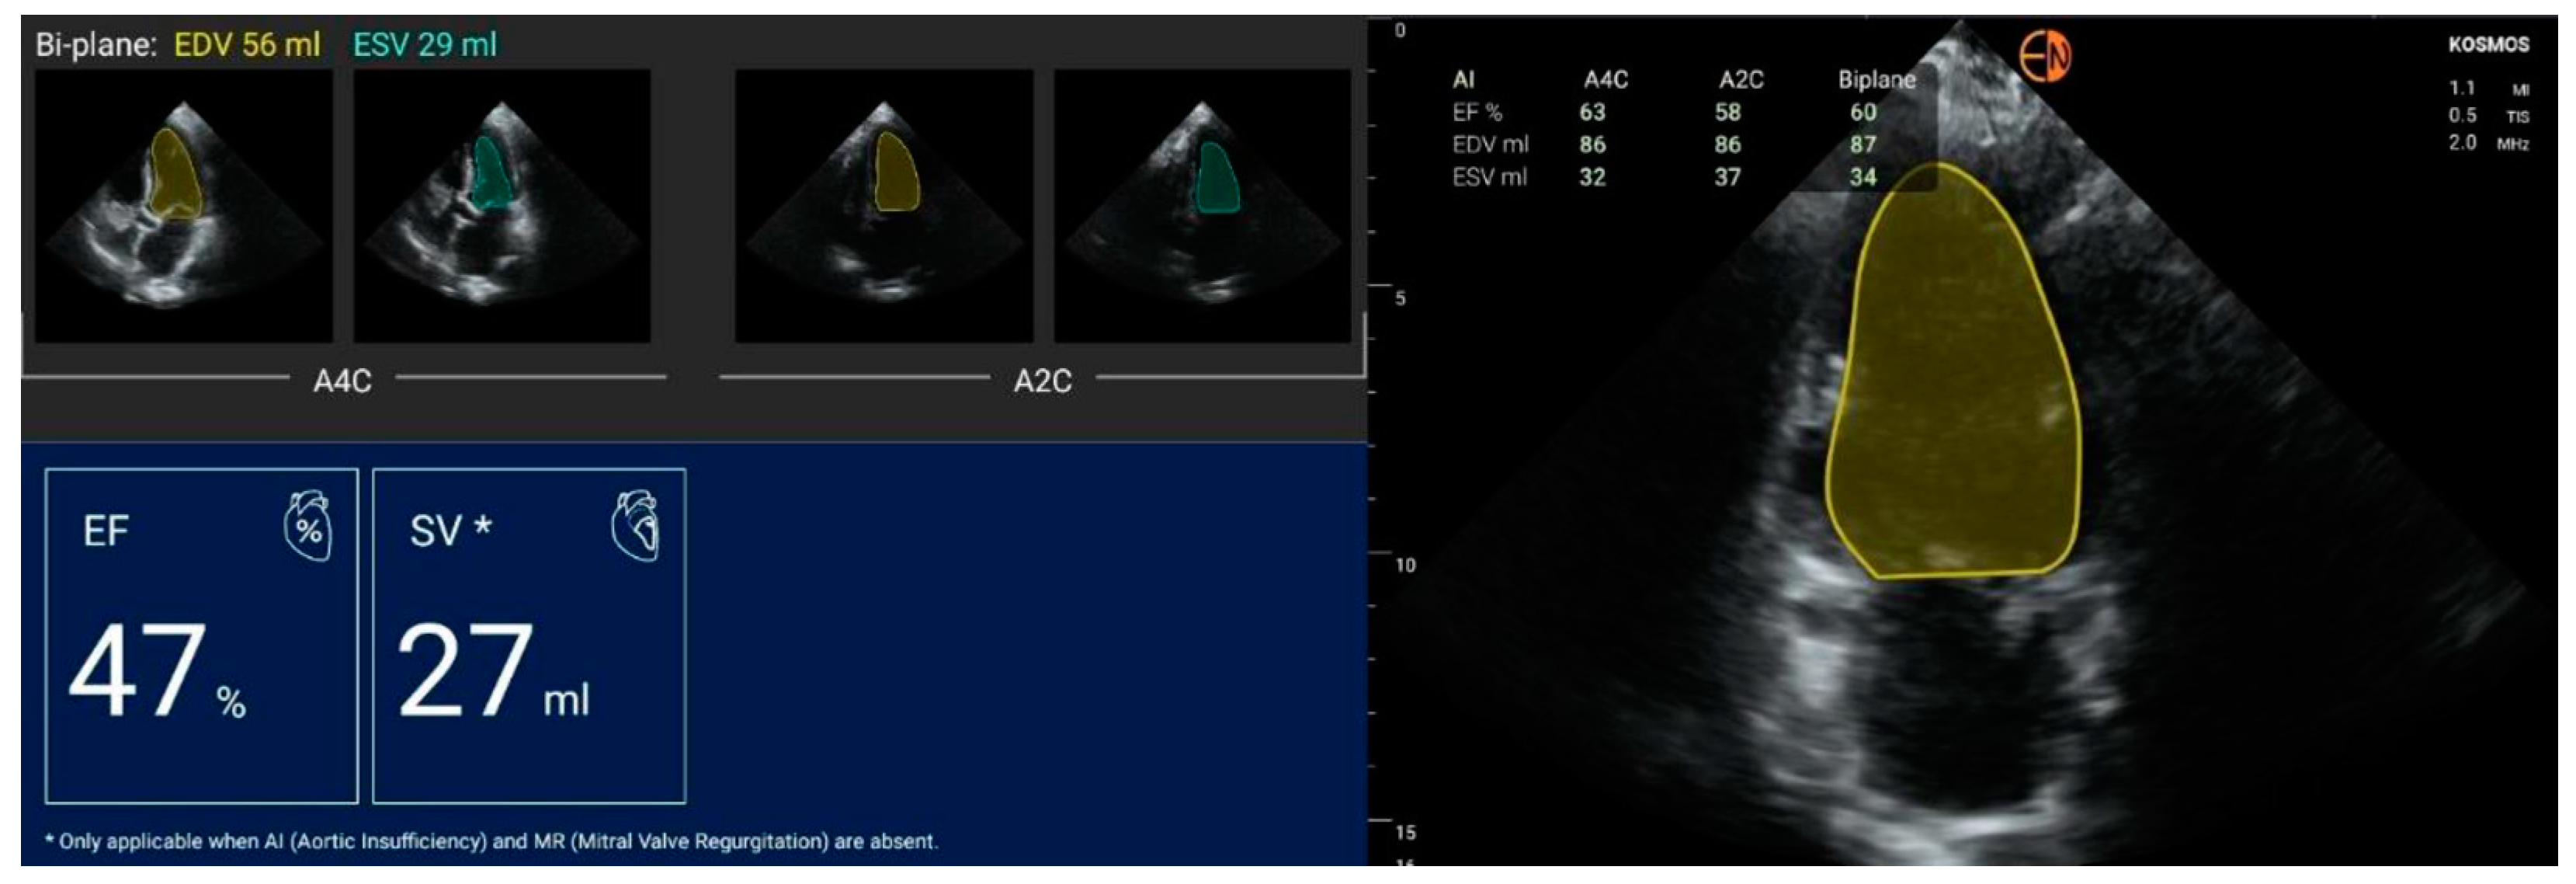

| FEVS (%) | mean (stdev) | 51.4 (9.1) | 51.7 (9.8) | −0.33 (4.96) | −0.3 [−10.1 to 9.4] |

| median [Q1 to Q3] | 53.5 [46 to 57] | 52.5 [48 to 58.5] | −1 [−3 to 4] | ||

| {min to max} | {30 to 67} | {26 to 68} | {−11 to 10} |